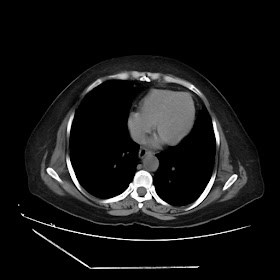

A 70 years old woman with Obstractive jaundice & palpable GB

Latest Radiological images: